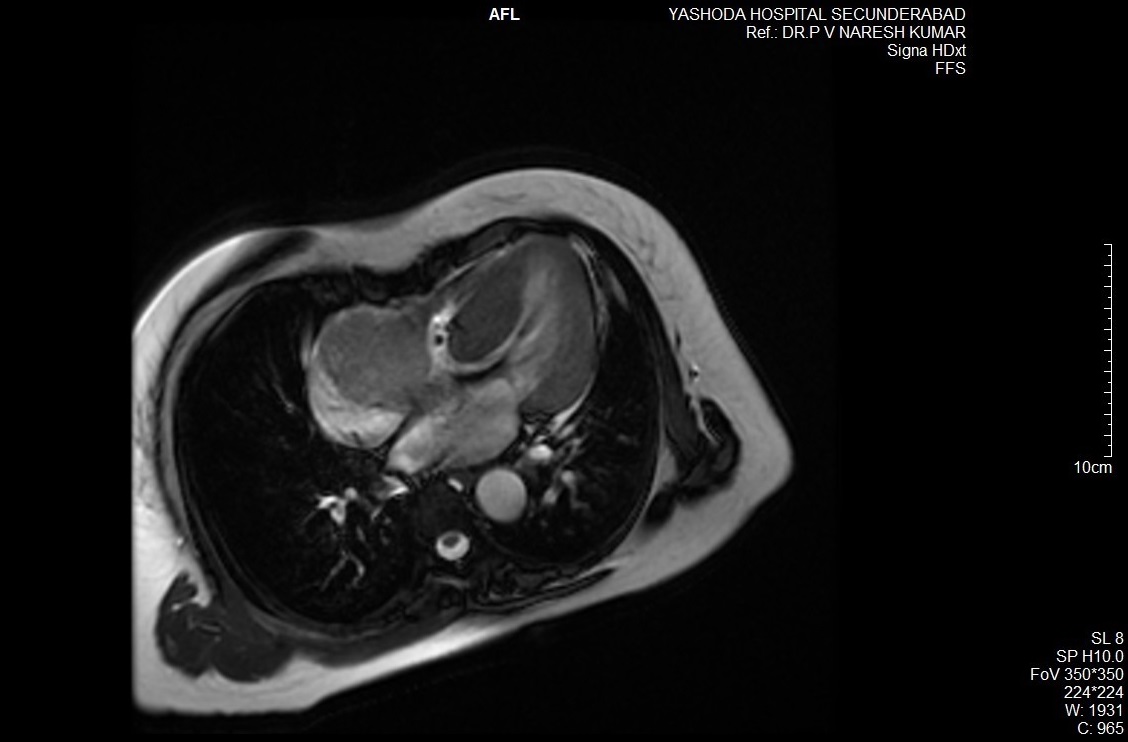

On further evaluation, the patient’s echocardiogram showed a 4.5 x 4.3 cm cystic tumor in the right atrium, hypertrophied obstructive cardiomyopathy with moderate left ventricular outflow tract obstruction, and good left ventricular function. She also underwent computed tomography (CT) and magnetic resonance imaging (MRI) of the chest, which revealed a neoplastic mass lesion, most likely right atrial myxoma.

Mediastinal paragangliomas are diagnosed by measuring urinary catecholamines and their metabolites, metanephrines and vanillylmandelic acid. Tumor localization is done with the help of CT, I-MIBG scintigraphy, and MRI. Because of the high vascularity of these lesions, contrast medium administration enhances CT.